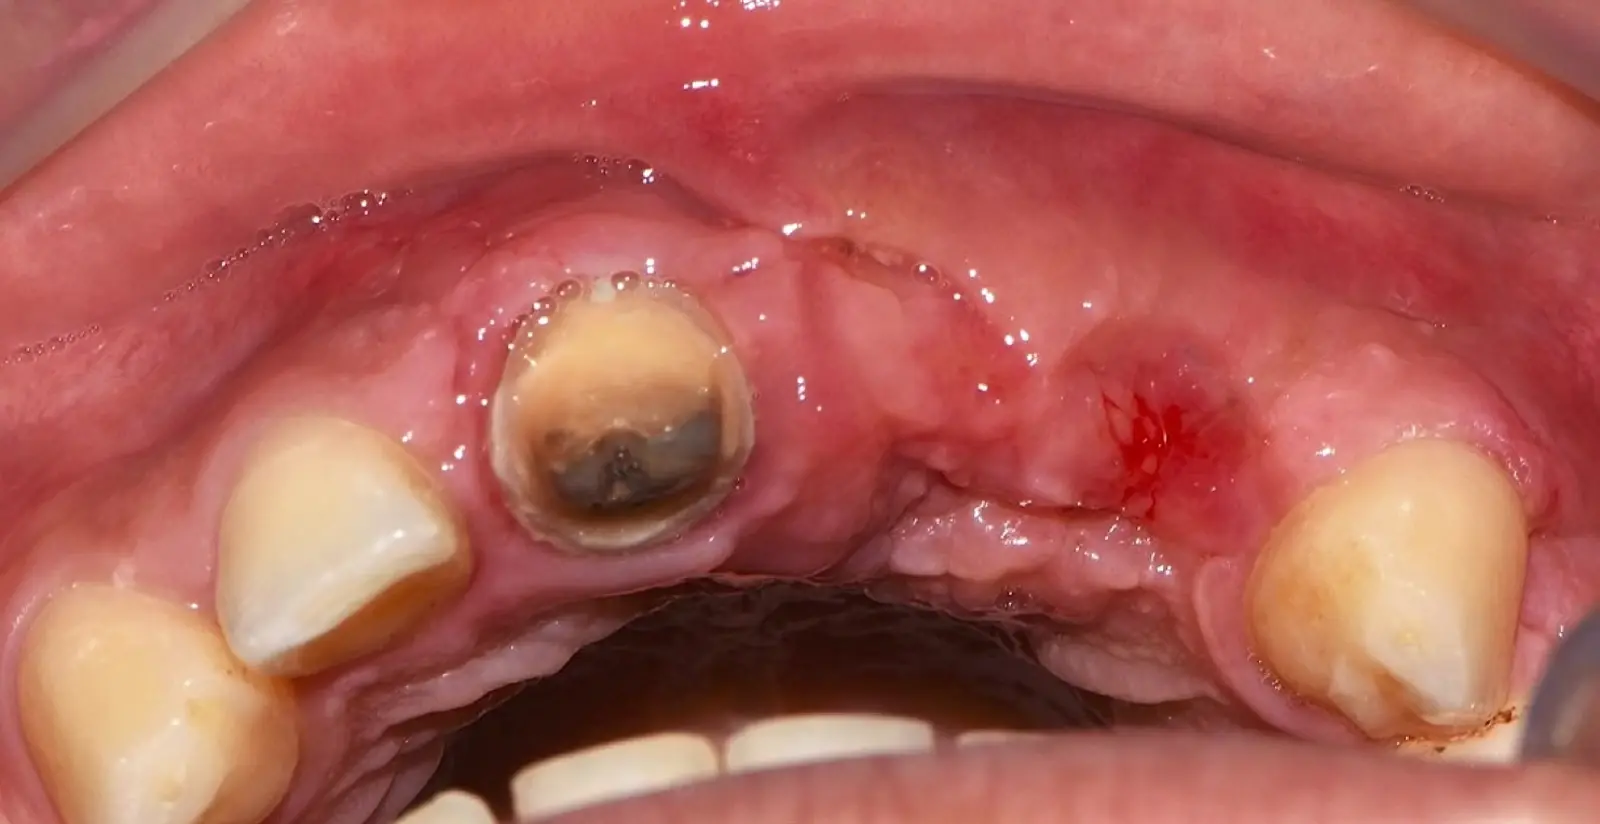

Paciente de sexo femenino de 53 años llega a la consulta solicitando una prótesis implantosoportada. En la evaluación clínica se observa un edentulismo total superior con una severa reabsorción ósea generalizada, a excepción de la pieza 2.3, que se encontraba en estado de remanente radicular. En la evaluación tomográfica se corrobora el hallazgo clínico y se indica una reconstrucción de reborde con injertos en bloque previo a la planificación de implantes dentales.

Figura 18. Vista clínica en la que se evidencia la deficiencia horizontal severa del reborde alveolar.

Paciente de sexo femenino de 36 años de edad, llega a la consulta por presentar una restauración protésica inadecuada. En el examen clínico se observa una restauración protésica provisional acrílica sobre las piezas 1.1 y 2.2. Adicionalmente, se aprecia recesión gingival a nivel de la pieza 2.2 y deficiencia horizontal severa de reborde a nivel de la zona edéntula correspondiente a la pieza 2.1. En la evaluación tomográfica se observa ausencia total de tabla ósea vestibular en la pieza 2.2, y se corrobora el déficit en la zona edéntula de la pieza 2.1, para lo cual se indica una reconstrucción de estructuras óseas con hueso en bloque de origen bovino y posteriormente la colocación de implantes dentales.

Figura 34. Vista frontal donde se observa deficiencia vertical del reborde óseo a nivel de las piezas 2.1, 2.2.